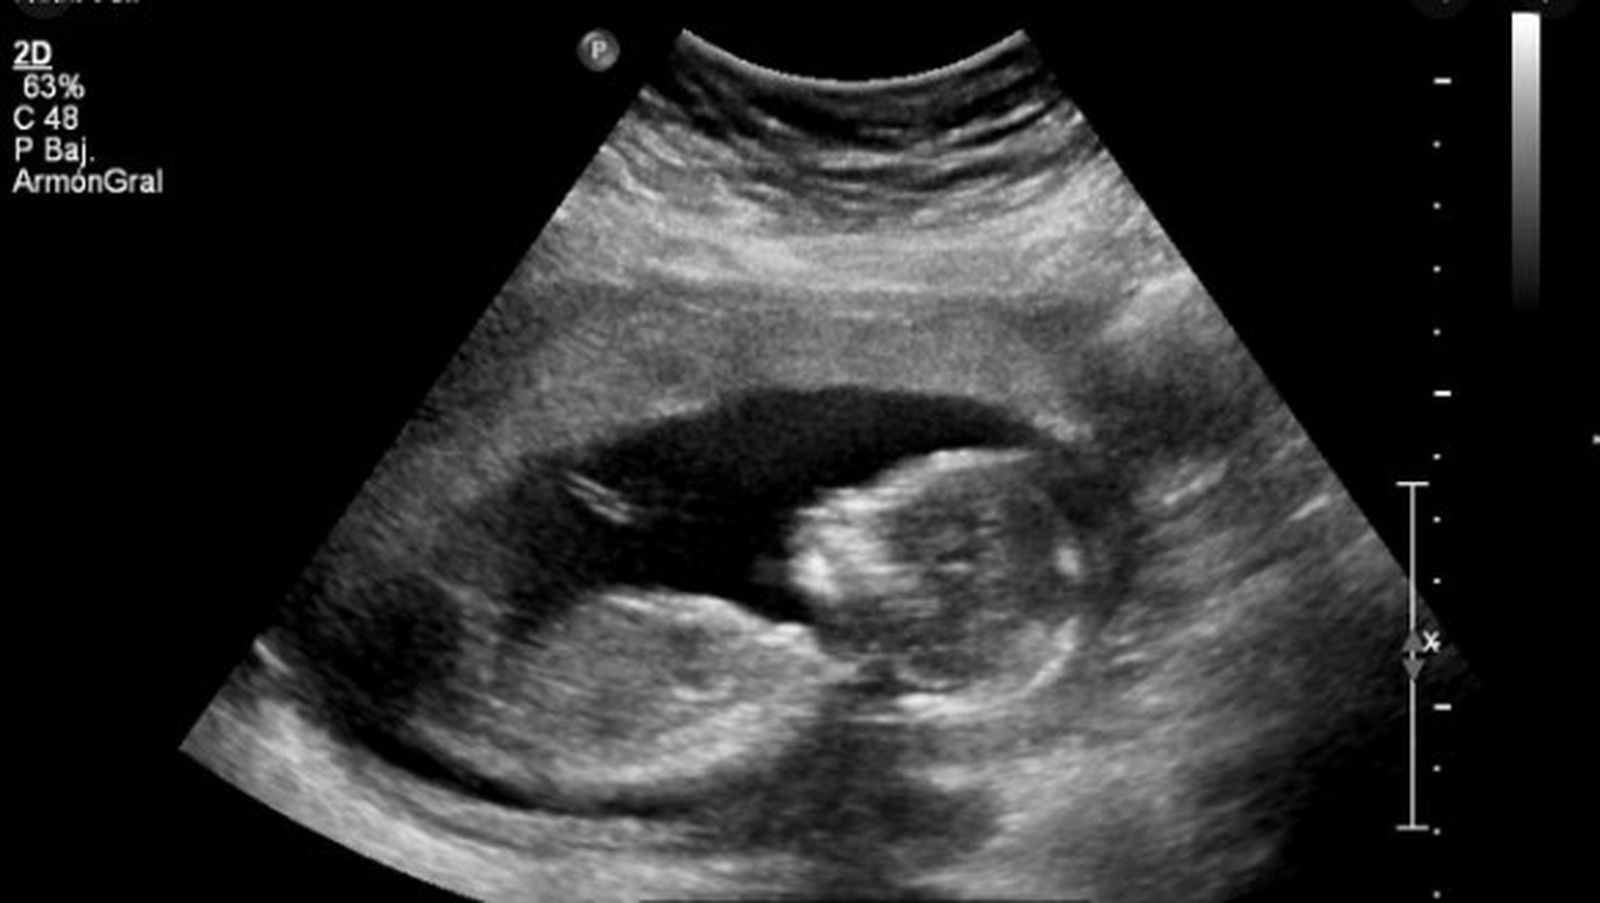

El aborto legal hasta la semana 14 de la gestación produjo en Argentina un jolgorio social en el sector feminista. Sin embargo, legalizar no cambia la calificación moral y ética de los actos. Legal no significa ético. Así, el salario mínimo, la dosis personal de droga, etc., pueden ser legales pero no son éticos. Como si desde la semana 14 el feto comenzara a ser humano. Es una pelea feminista que desconoce la dignidad de niñas y niños no nacidos. El machismo arraigado en el mundo produce las peleas equivocadas por la igualdad de género. También en ciertas peleas dentro de la Iglesia... Pero en este caso, no se trata de una lucha por la igualdad de género. Niñas y niños indefensos mueren.

En la semana 14 de embarazo, “el bebé ya ha adquirido una apariencia totalmente humana. Sus rasgos faciales ya están perfectamente definidos, los ojos y las orejas ya se encuentran en su ubicación final y aparecen las cejas y sus primeros cabellos. El feto ya depende totalmente de la placenta, que ya tiene un tamaño mayor que él, para su alimentación. Ahora, el feto ya mide entre ocho y nueve centímetros y su peso es de unos 43 gramos. El cerebro sigue desarrollándose rápidamente y su cabeza representa casi la mitad de su tamaño total. A partir de esta semana, el ginecólogo ya puede medir las partes básicas del bebé, como la cabeza, el abdomen o el fémur, por separado. El sistema nervioso central del bebé, que incluye el cerebro y la columna, ya tiene sus componentes básicos y las conexiones entre células nerviosas individuales se vuelven más organizadas” (https://mibebeyyo.elmundo.es/embarazo-semana-semana/semana-14-del-embarazo).